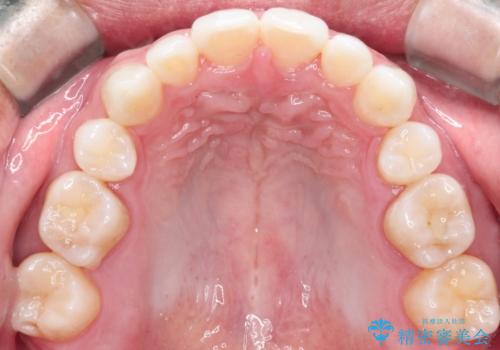

【インビザライン】笑った時の歯並びを綺麗にしたい

- 笑った時の歯の見え方を綺麗にしたいことを主訴に来院されました。

インビザラインにて治療を行なっております。

シミュレーションを用いてることで患者さんと最終的なゴールを確認し行いながら治療を行うことができます。